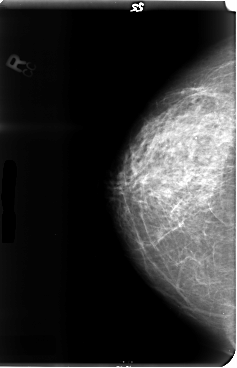

B_3042_1.LEFT_MLO

LEFT_CC LINES 4776 PIXELS_PER_LINE 3080 BITS_PER_PIXEL 12 RESOLUTION 50 OVERLAY

LEFT_MLO LINES 4712 PIXELS_PER_LINE 3144 BITS_PER_PIXEL 12 RESOLUTION 50 OVERLAY

FILE: B_3042_1.LEFT_MLO.OVERLAY

TOTAL_ABNORMALITIES 1

ABNORMALITY 1

LESION_TYPE MASS SHAPE IRREGULAR MARGINS OBSCURED-ILL_DEFINED

ASSESSMENT 3

SUBTLETY 2

PATHOLOGY MALIGNANT

TOTAL_OUTLINES 1

BOUNDARY